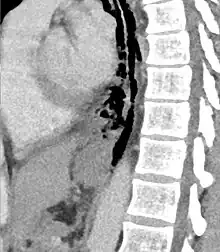

| Axial CT image through the upper chest showing extraluminal air (Pneumomediastinum) surrounding the trachea and esophagus | |

The diagnosis of Boerhaave syndrome is suggested on the plain chest radiography and confirmed by chest CT scan. The initial plain chest radiograph is almost always abnormal in patients with Boerhaave syndrome and usually reveals mediastinal or free peritoneal air as the initial radiologic manifestation. With cervical esophageal perforations, plain films of the neck show air in the soft tissues of the prevertebral space.

Hours to days later, pleural effusion(s) with or without pneumothorax, widened mediastinum, and subcutaneous emphysema is typically seen. CT scan may show esophageal wall edema and thickening, extraesophageal air, periesophageal fluid with or without gas bubbles, mediastinal widening, and air and fluid in the pleural spaces, retroperitoneum or lesser sac.